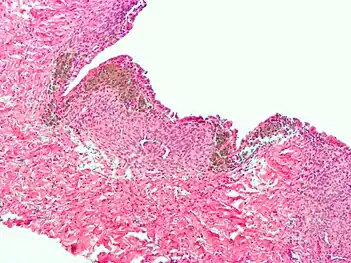

Histopathology

For a histopathological diagnosis, at least two of the following three criteria should be present:[110]

Immunohistochemistry has been found to be useful in diagnosing endometriosis as stromal cells have a peculiar surface antigen, CD10, thus allowing the pathologist go straight to a staining area and confirm the presence of stromal cells and sometimes glandular tissue is identified that was missed on routine H&E staining.[111]